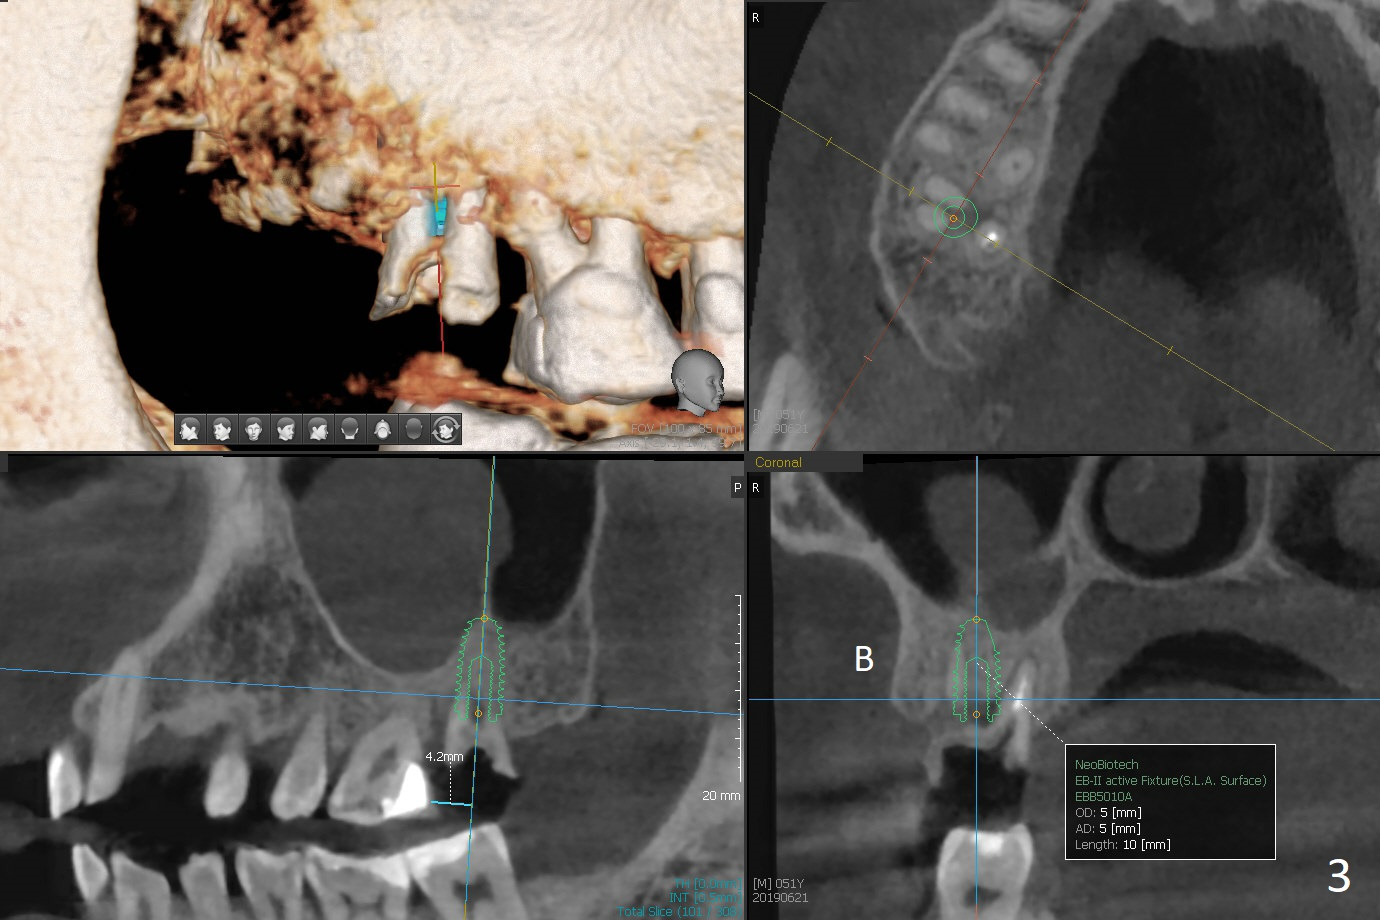

A 51-year-old man agrees to have #2 residual root to be extracted for implant. Panoramic X-ray (Fig.1) and CT coronal section (Fig.2) show maxillary sinus mucocele (*). A 5x10 mm implant will be placed not to intrude into the sinus (Fig.2,3). In case sinus membrane perforation, prepare PRF membranes for repair. The apex of the implant will be engaged to an apparent sinus septum for stability (Fig.4,5,7 arrowheads). Fig.4,5,6 are sagittal and coronal sections and 3-D image of Fig.3 without an implant at #2, while Fig.7 is the inferior view of Fig.6 (arrow).